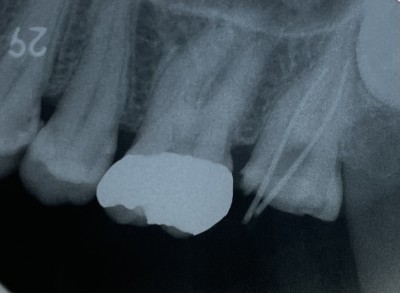

【下顎大臼歯根管治療】

2023.06.16 症例紹介